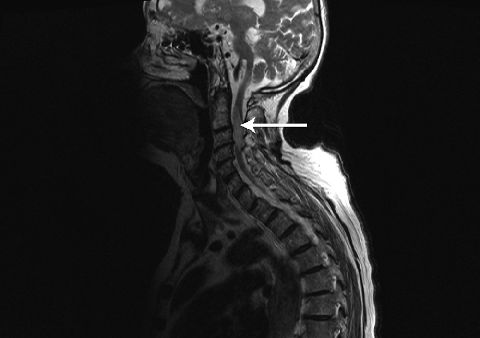

About 10 days after the onset of weakness, a neurologist diagnosed a cervical myelopathy and recommended magnetic resonance imaging of the spine. This revealed an area of inflammation at C2–C4 involving the full thickness of the spinal cord at that level, consistent with transverse myelitis (Figure). She was diagnosed with herpes zoster myelitis.

Diagnosing HZM can be challenging. The importance of a careful clinical assessment to establish the likelihood of this diagnosis and the level of the spinal cord damage, in combination with confirmatory magnetic resonance imaging (MRI)7cannot be overstated. MRI not only provides information about the site but also the extent of spinal cord involvement, and excludes other possible diagnoses. In our patient, HZM was diagnosed based on the temporal relationship of myelopathy to the rash and MRI findings. Although the area of the spinal cord that was involved on the MRI scan was less extensive than that affected by the herpetic rash, we do not see this as clinically inconsistent.